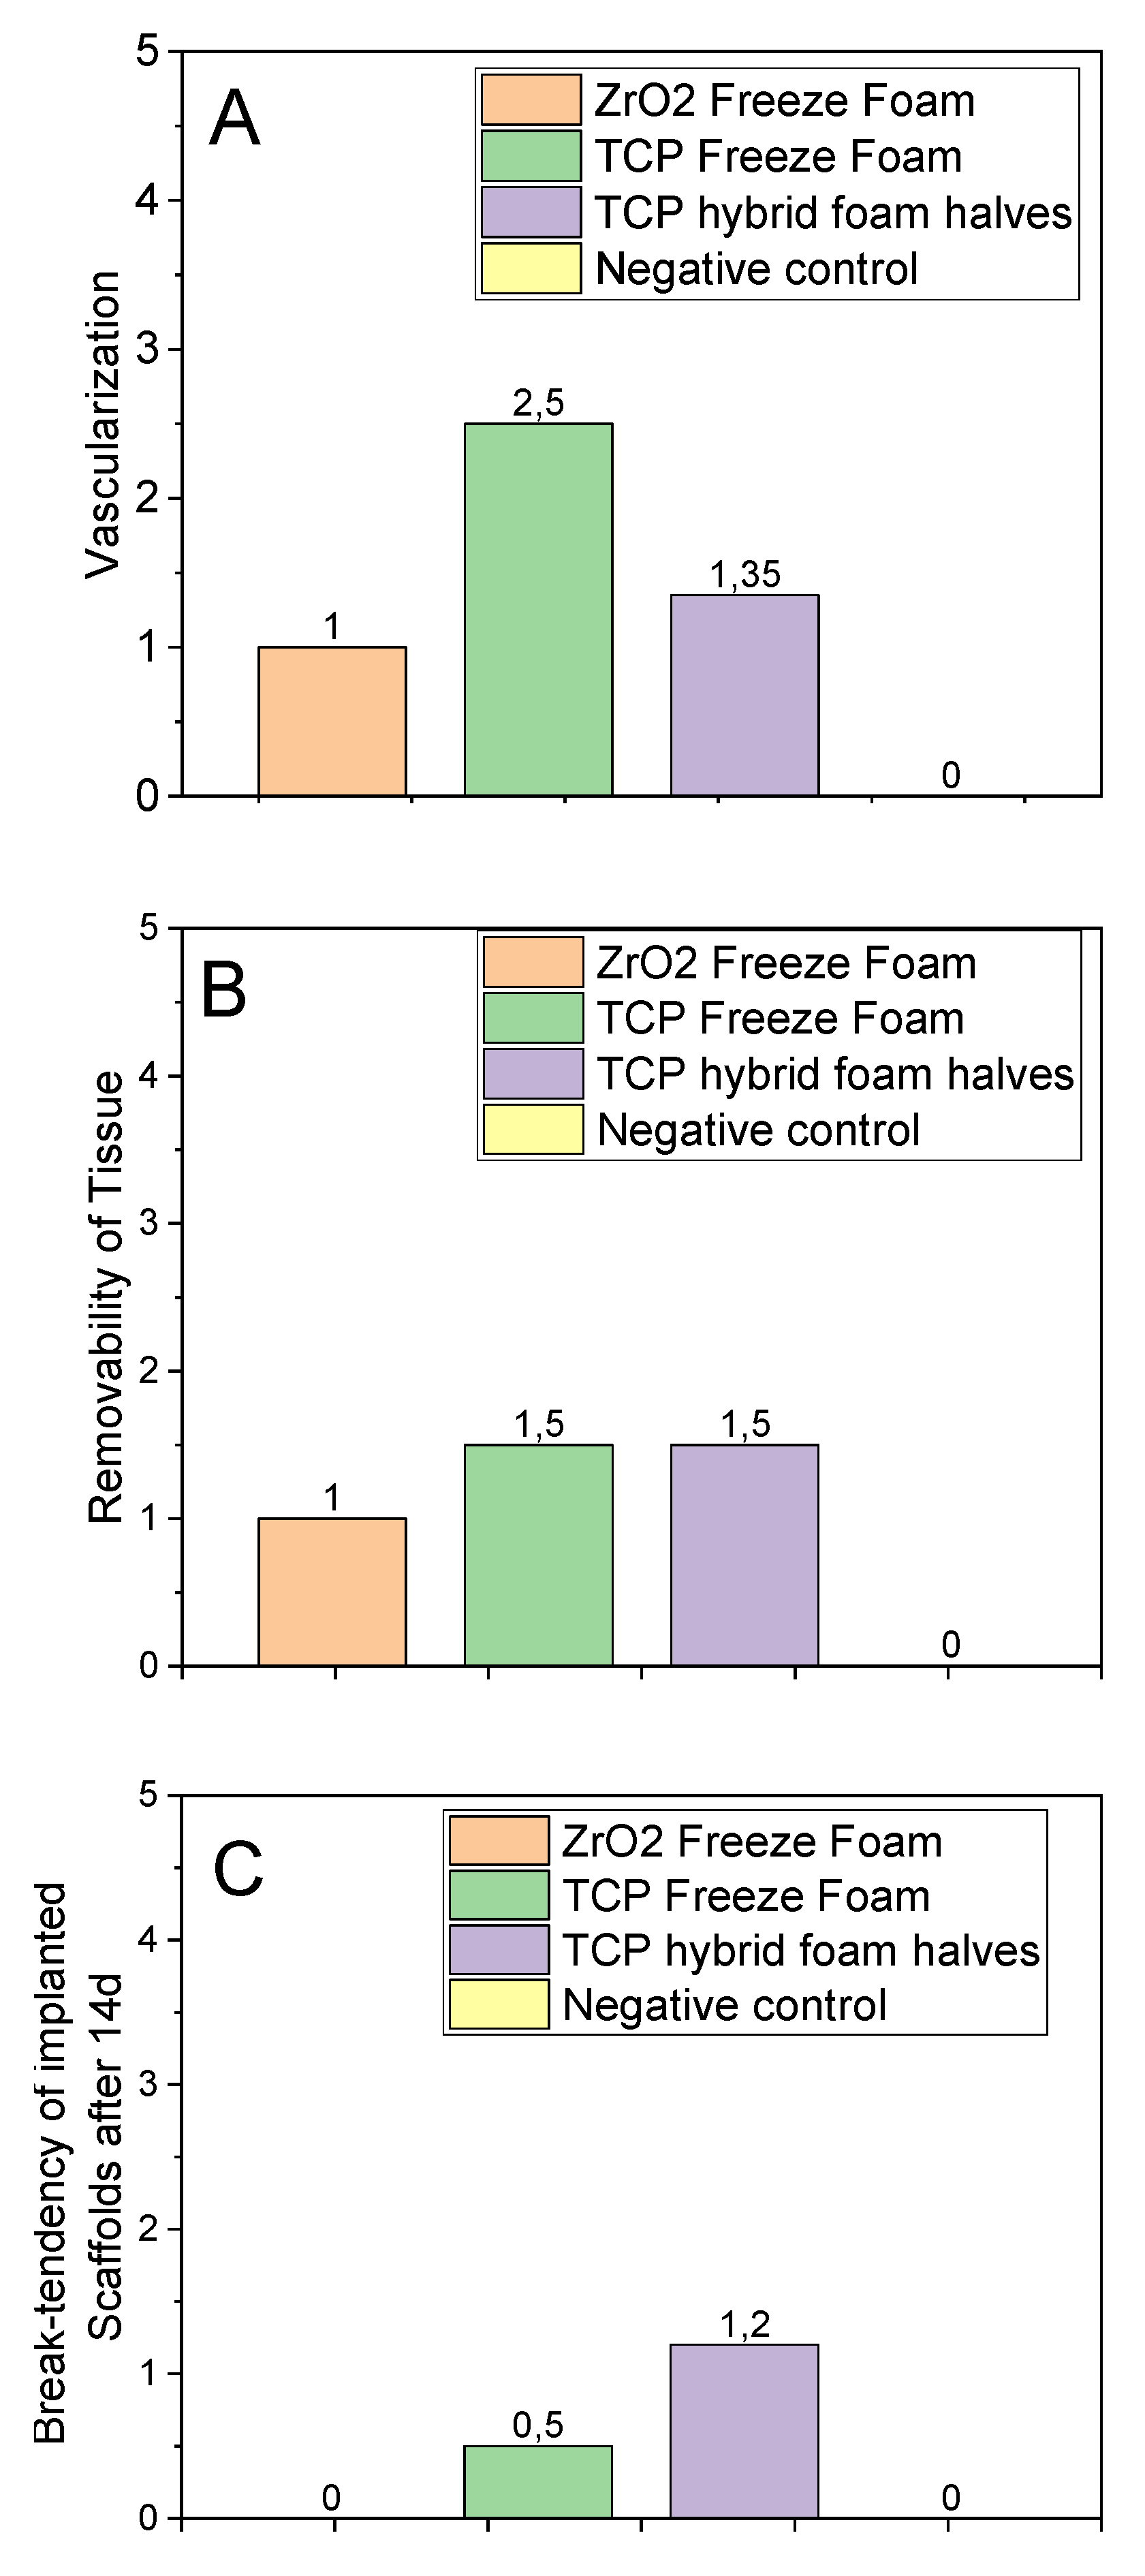

3.4.4. Implant Parameters

3.4.5. In Vivo Conclusion